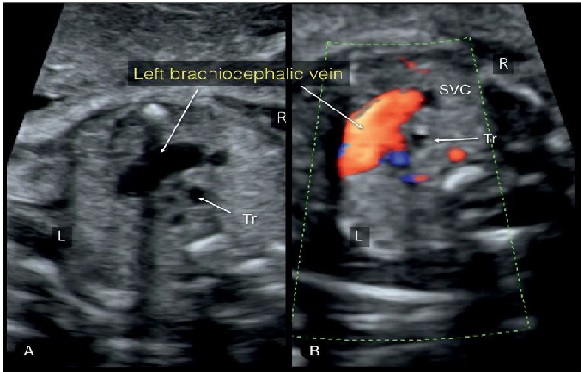

Hình 10: Doppler màu mặt cắt ngang ngực thai nhi ở mức tĩnh mạch cánh tay đầu trái (Left branchiocephalic vein) của thai nhi TAPVR thể trên tim. Hình ảnh thể hiện sự ra tăng lưu lượng máu từ tĩnh mạch phổi. Chú ý Doppler màu (B) thể hiện chiều dòng chảy trong tĩnh mạch cánh tay đầu từ trái qua phải về phía tĩnh mạch chủ trên (SVC). So sánh với tĩnh mạch cánh tay đầu bình thường (Hình.11). Tr: khí quản; L: trái; R: phải.

Hình 11: A & B mặt cắt ngang vị trí trung thất trên, cao hơn so với mặt cắt 3 mạch máu-khí quản. Hình ảnh tĩnh mạch cánh tay đầu trái (left brachiocephalic vein - LBCV). Chú ý vị trí giải phẫu của tĩnh mạch cánh tay đầu trái: Tuyến ức (Thy) ở phía trước và 3 động mạch tay đầu (three brachiocephalic arteries - BCA) ở phía sau. Tr: khí quản; L: trái; R: phải.